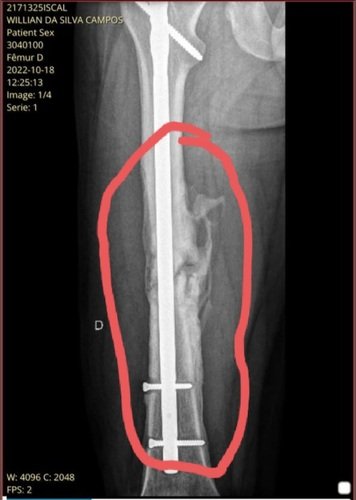

Oii, meu nome é Willian, sou portador de Osteomielite Crônica à 1 ano e 2 meses, já passei por 4 cirurgias, mais de 70 dias internado, muitos antibióticos e muito sofrimento, peguei uma bactéria no osso após uma cirurgia de fratura no Fêmur e só foi diagnosticado depois de meses por outro médico, agravando ainda mais a Infecção, desde então venho sofrendo e lutando contra essa doença terrível que está acabando com o meu osso aos poucos, no SUS dizem não ter cura, mas para Deus e um especialista em infecção ortopédica que aceitou pegar meu caso, tem cura sim, porém o tratamento é cirúrgico e tem um alto custo, 90.000,00. A doença vem se agravando e corro sérios ricos, o medo de perder a perna está acabando comigo. Mas vamos pensar pelo melhor 🙏🏻